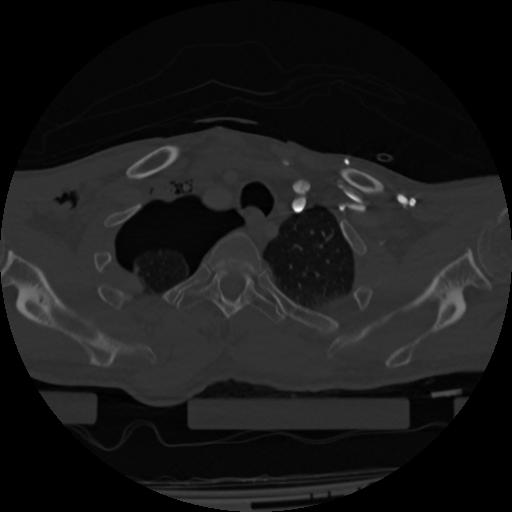

22 ANGIO,CE,Vol,0.5,ANGIO,,